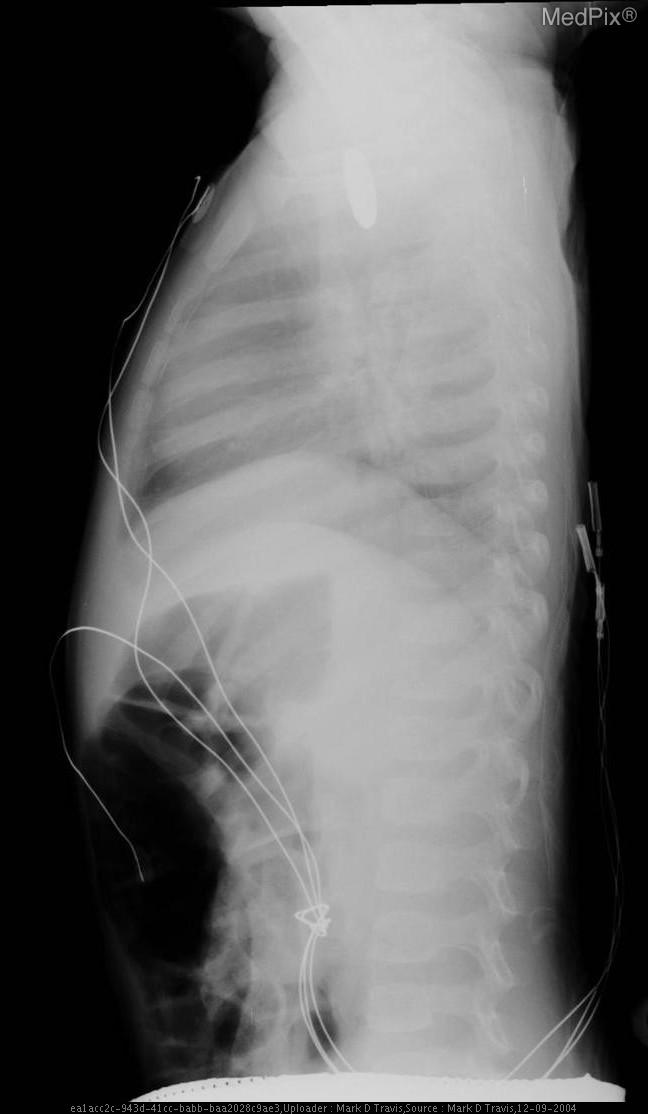

Esophageal foreign body - Coin ingestion

- Age: 1

- Sex: Male

- Modality: X-ray

- Region: Chest

- Diagnosis: Esophageal foreign body

- Frontal chest X-ray in a pediatric patient shows a round, well-defined radiopaque object projected over the upper thoracic region, likely within the midline.

- The object is seen in the region posterior to the trachea and anterior to the vertebral column, consistent with the expected course of the esophagus.

- No evidence of double halo or step-off suggesting a button battery (appears uniform in density).

- The cardiac silhouette and diaphragm contours are within normal limits.

- Lungs are clear without focal consolidation, pneumothorax, or effusion.

- Bony structures appear intact, no acute fractures noted.

- No subcutaneous emphysema or soft tissue gas.

- Several monitoring leads and lines seen externally, no invasive lines visualized.

Esophageal foreign body (radiopaque coin) in the upper thoracic esophagus. The central, midline location on this frontal image and the uniform circular density without polarity markers (seen in coins rather than button batteries) strongly suggest a coin lodged in the esophagus rather than the trachea (which typically lies anteriorly and shows overlapping on lateral projection). Context consistency: Consistent, as the provided context describes coin ingestion in a 1-year-old male. Confidence: 95%